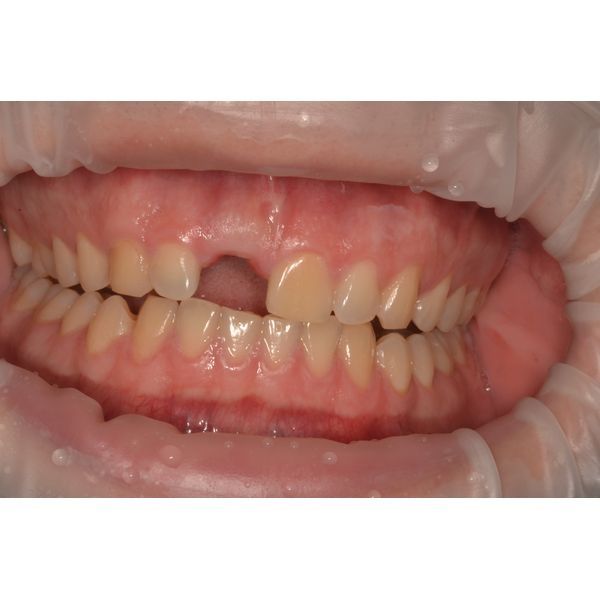

При осмотре полости рта обнаружено, что зуб 1.1 запломбирован, прощупывание переходной складки безболезненное. Определялась подвижность зуба 2-й степени (движение заметно, но в пределах физиологии). Слизистая оболочка полости рта бледно-розового цвета, без патологических изменений.

Патологический перелом зуба 1.1.